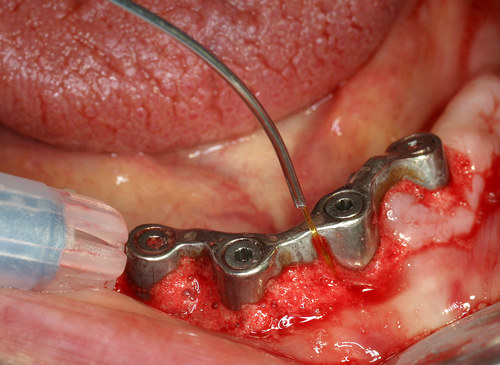

Cette maladie infectieuse est traitée avec un rayonnement laser pénétrant après une préparation initiale et une oxygénation des tissus. (fig.27)

Fig. 27

Traitement décontaminant sous eau oxygénée à 10 volumes